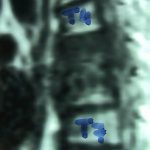

Εικ. 4: Μαγνητική τομογραφία της Θ.Μ.Σ.Σ. εγκάρσια λήψη, ακολουθία Τ1 & Τ2

Διαπιστώνεται η καταστροφή του μεσοσπονδυλίου δίσκου, φλεγμονώδεις περισπονδυλικές μάζες πλαγίως και προσθίως και οπισθίως ύπαρξη επισκληριδίου αποστήματος